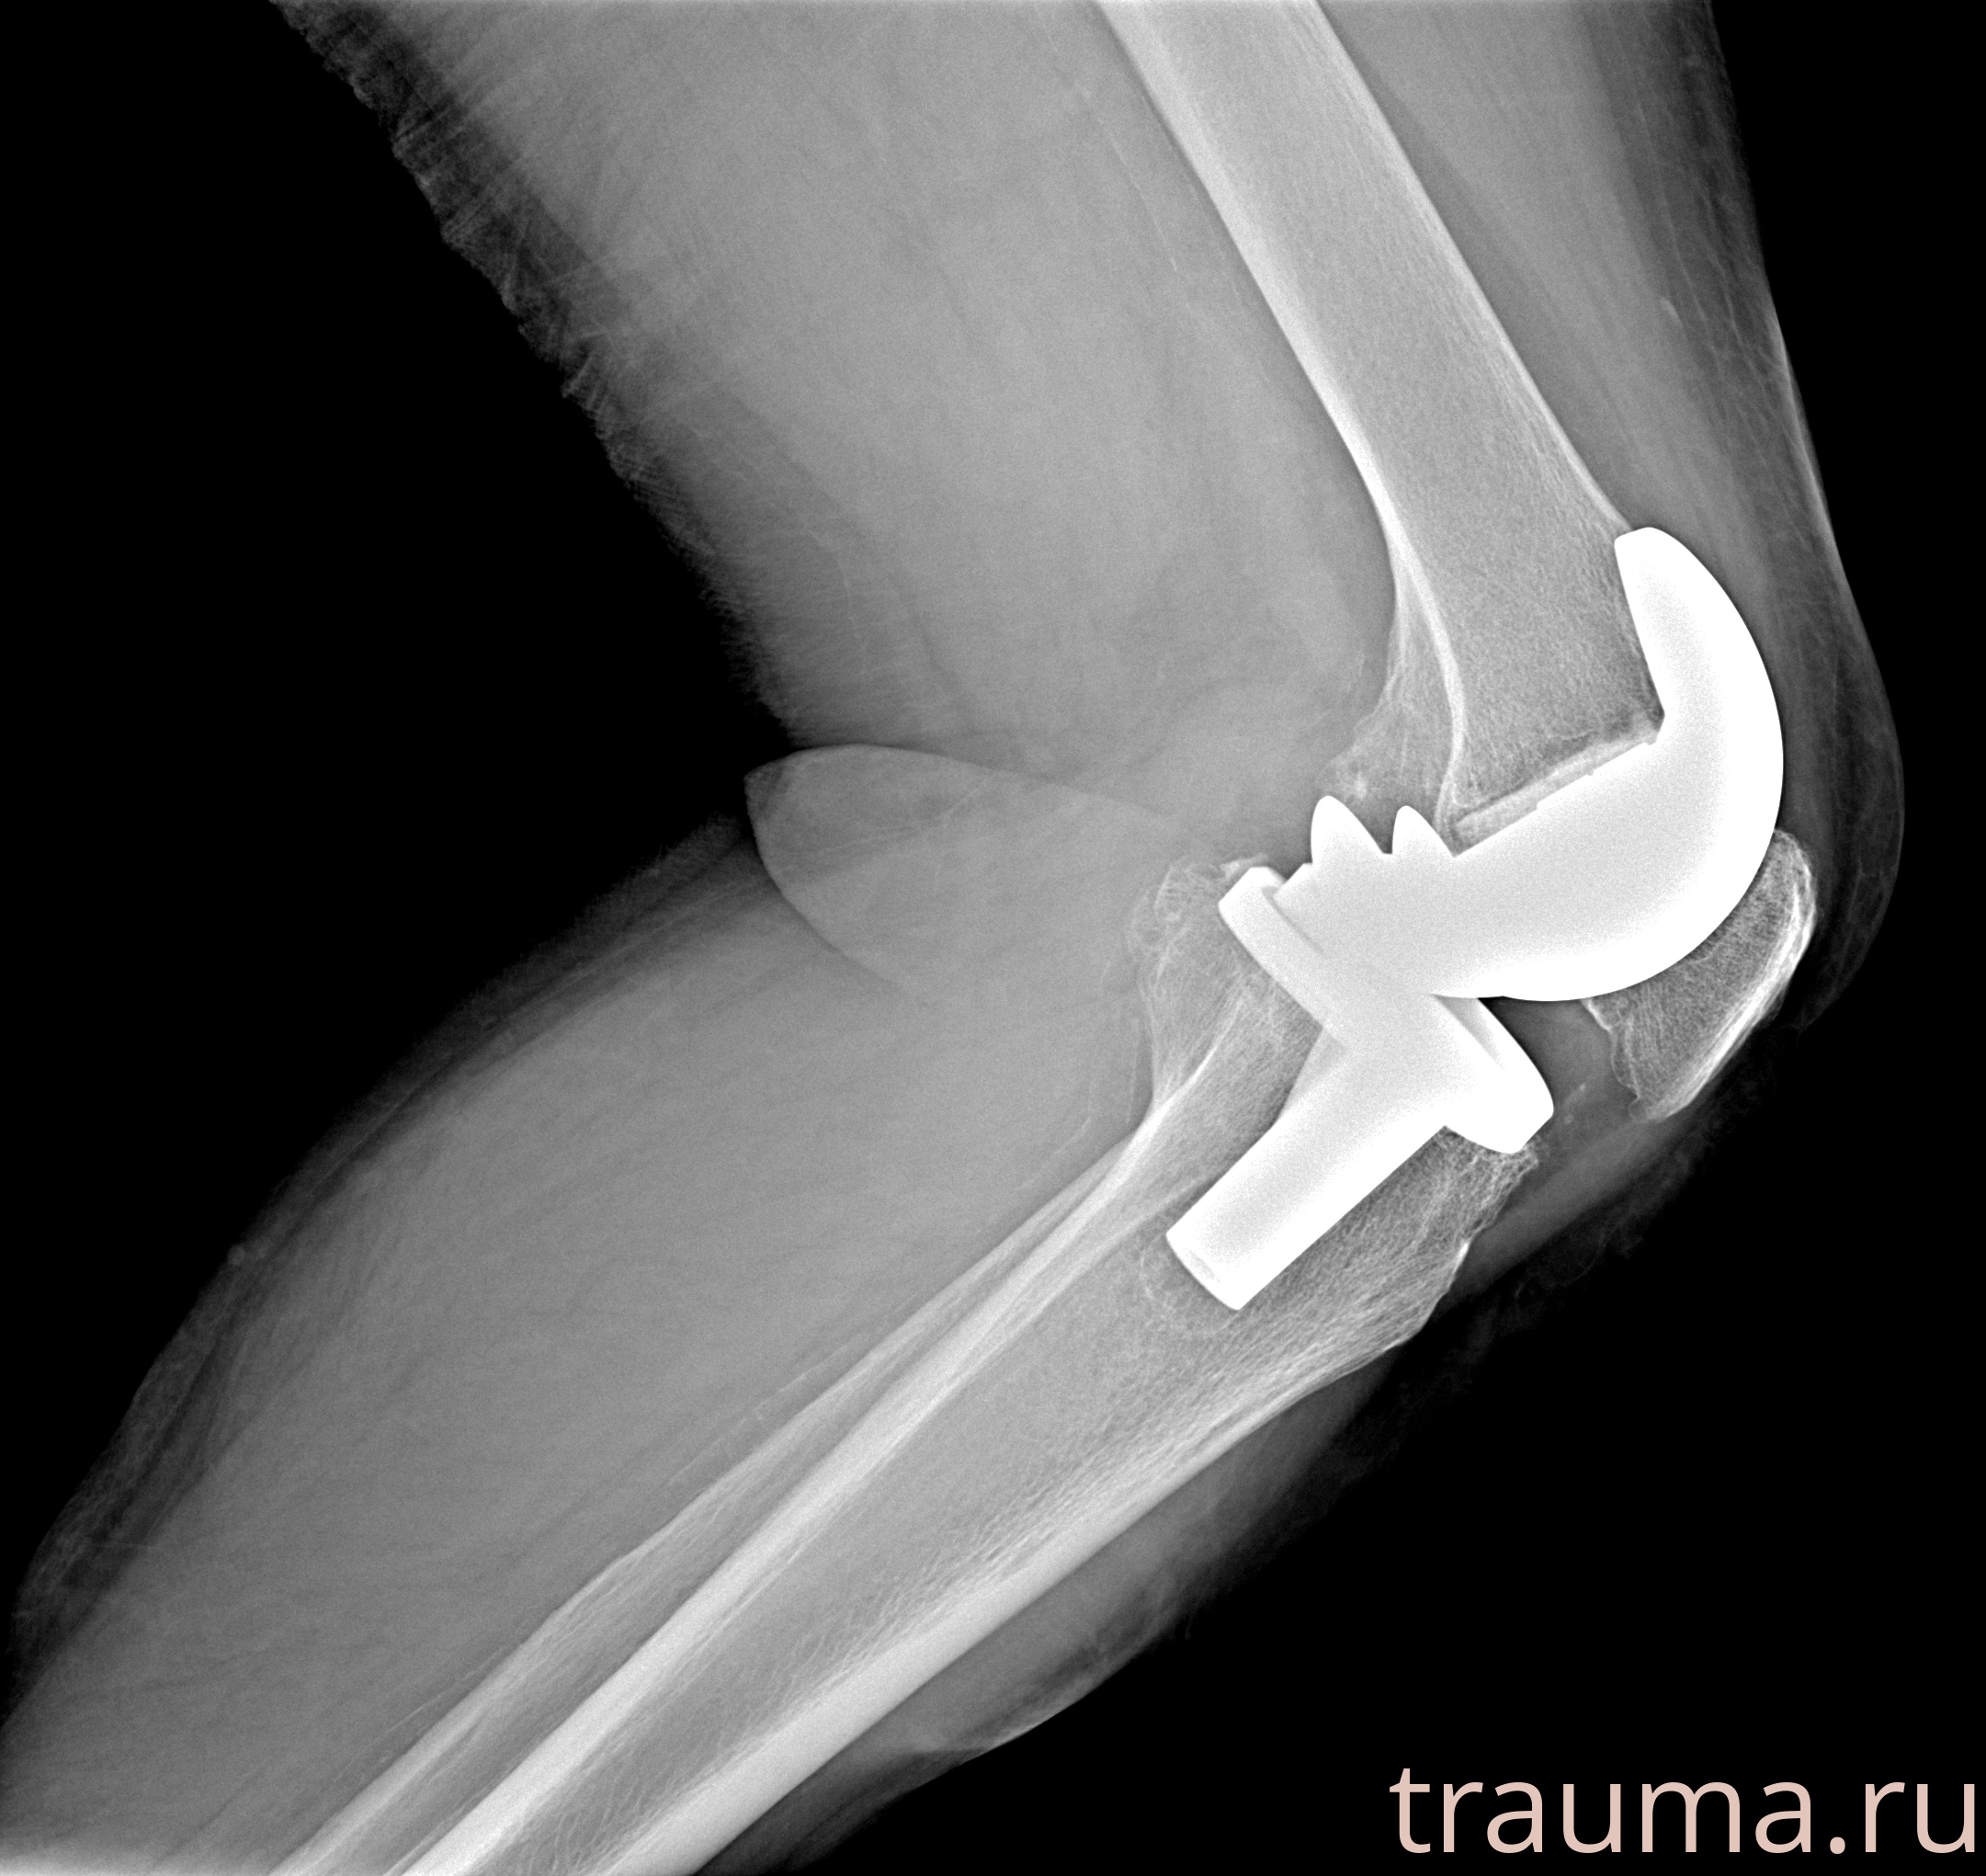

Рентгенограммы